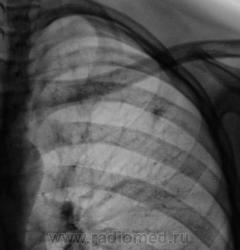

Первый срез.

Второй срез.

Третий срез.

А рентгенологически, что выставлять? Очаговый?

Два сегмента очаговый, больше двух диссеминир.

м.б.реальная картинка выглядит по -другому,но в туб. дисп. б-го направлять не с чем. я бы сделала лордоз и получила бы срез сосуда(сосуд.мальформация),тк достоверных очагов на тмг не получ.м.б назнач. бы контроль ч\з 3 мес. причины "играть" в кт не было.

Конечно, ответственность, подросток и все такое... Но с другой стороны, кроме мелкого кальцинатика прицепиться больше не к чему. Все очаговоподобные тени видны при уменьшенной яркости и в местах пересечения сосуда с кортикалом ребра. Либо имеют "хвостик", что указывает на сосуд. Такое мое мнение.